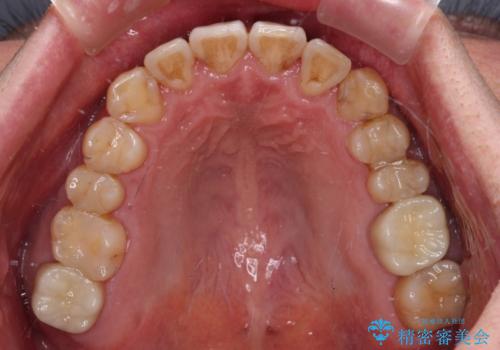

- 虫歯が多く、セラミッククラウンにより虫歯治療を行っている途中で矯正治療をしたいとのことで来院された患者様です。

上顎前歯が舌側に転位しており、なるべく早く楽に矯正したいとのことで、ワイヤー矯正を行うこととしました。

虫歯治療途中の歯は仮歯が装着されていたため、そのまま矯正治療を行い、矯正後に補綴治療を行うこととしました。

インビザライン矯正では苦手とする舌側転位した前歯をスムーズに改善することができました。

矯正治療により歯磨きがしやすくなったので、虫歯予防のセルフケアが行いやすい環境となりました。